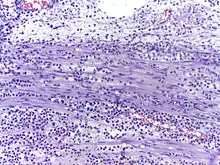

In autopsy, the presence of neutrophils in the heart or brain is one of the first signs of infarction, and is useful in the timing and diagnosis of myocardial infarction and stroke.

Neutrophils are seen in a myocardial infarction at approximately 12–24 hours,[59] as seen in this micrograph.